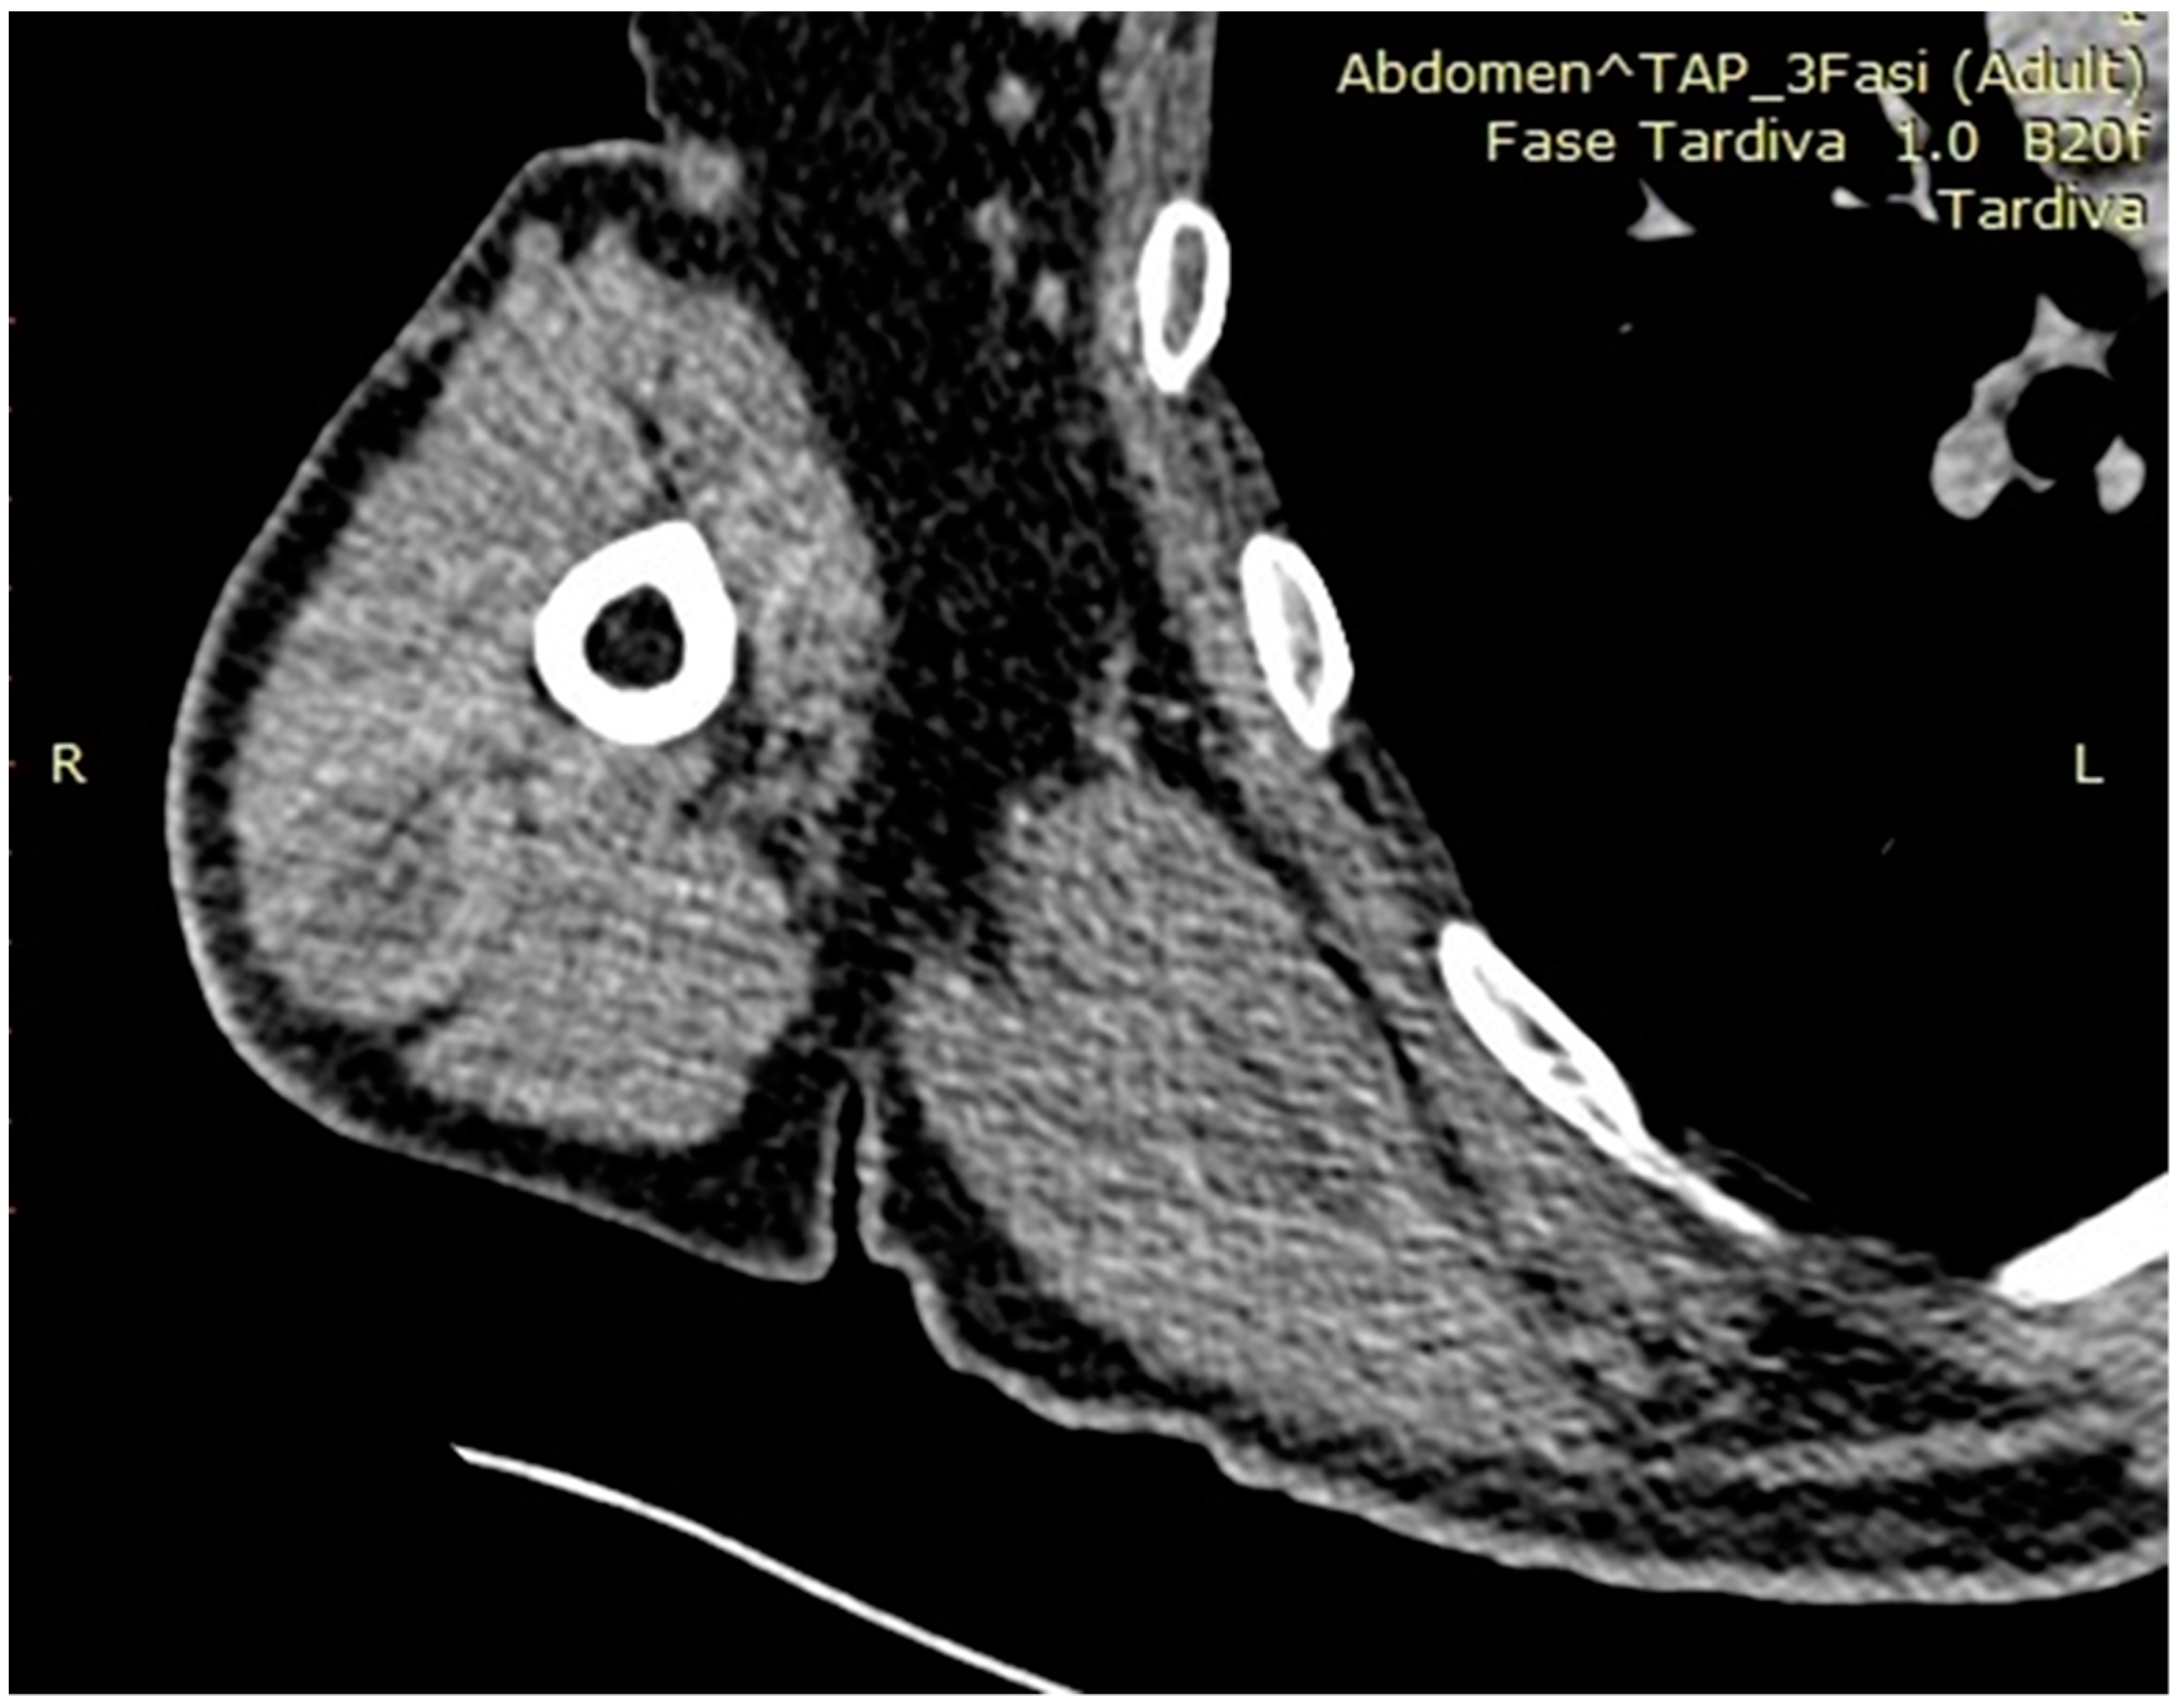

:1. Introduction

2. Materials and Methods

3. Results